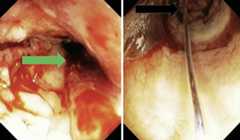

Fig. 1.

Rectal stricture 10 cm from the anus, not allowing the endoscope to pass (blue arrow).